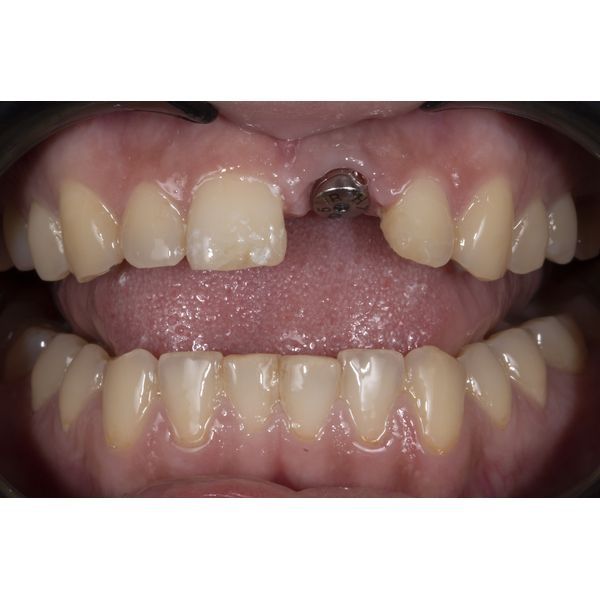

Провели совместную консультацию со стоматологом-хирургом, где приняли решение выполнить имплантацию зуба. Установили имплантат Osstem Regular 0.4 10 мм, а также изготовили временную коронку на него для коррекции эстетики. Следующий приём назначили через 4 месяца.

Когда имплант в кости стабилизировался, выполнили рентгенологическое исследование, чтобы оценить его приживаемость и затем провести протезированием зуба. Также предварительно отсканировали верхнюю челюсть и спроектировали будущую улыбку, далее выбрали конструкцию: циркониевую покрывную коронку с облицовкой на индивидуальном абатменте. Также провели художественную реставрацию сколотых центральных зубов с учётом заранее смоделированной улыбки пациентки.